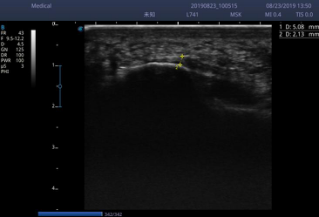

女士足跟部压痛明显,双侧足弓塌陷(图 4),足底压力测试发现足扁平(图 5),接着进行了足底超声检查,提示左侧足底筋膜厚度较右侧明显增厚(图6,7)。康复医生给予明确的诊断足底筋膜炎炎。

李女士平素工作繁忙,没有足够的时间来医院做物理治疗,所以选择了可视化超声引导下药物注射的治疗方法(图8),注射后1周VAS评分从8分下降至2分,之后配合康复锻炼,同时配置了足底矫形鞋垫(图9),1月后足跟疼痛完全消失。

图7:左侧足底筋膜厚度5.08mm

图8:右侧足底筋膜厚度2.13mm